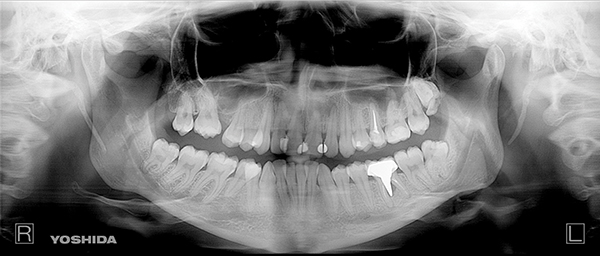

Intraoral evaluation showed compromised oral health with generalized gingivitis and plaque accumulation (Figure 2). Many teeth had already been restored, and several restorations were failing. The maxillary dental midline coincided with the facial midline with a minor inclination. The lower midline deviated approximately 3 mm to the left side in reference to the upper midline. There was moderate crowding in the maxilla, mainly on the right side, and severe crowding in the mandible. Canines on the right were in Angle class III malocclusion, while molars and canines on the left were in mild class II malocclusion. Radiographic evaluation revealed crowding, missing teeth, and failing restorative as well as endodontic treatment (Figure 3).

Fig 3. Preoperative panoramic radiograph revealing tooth crowding and several failing restorations.

Figure 3